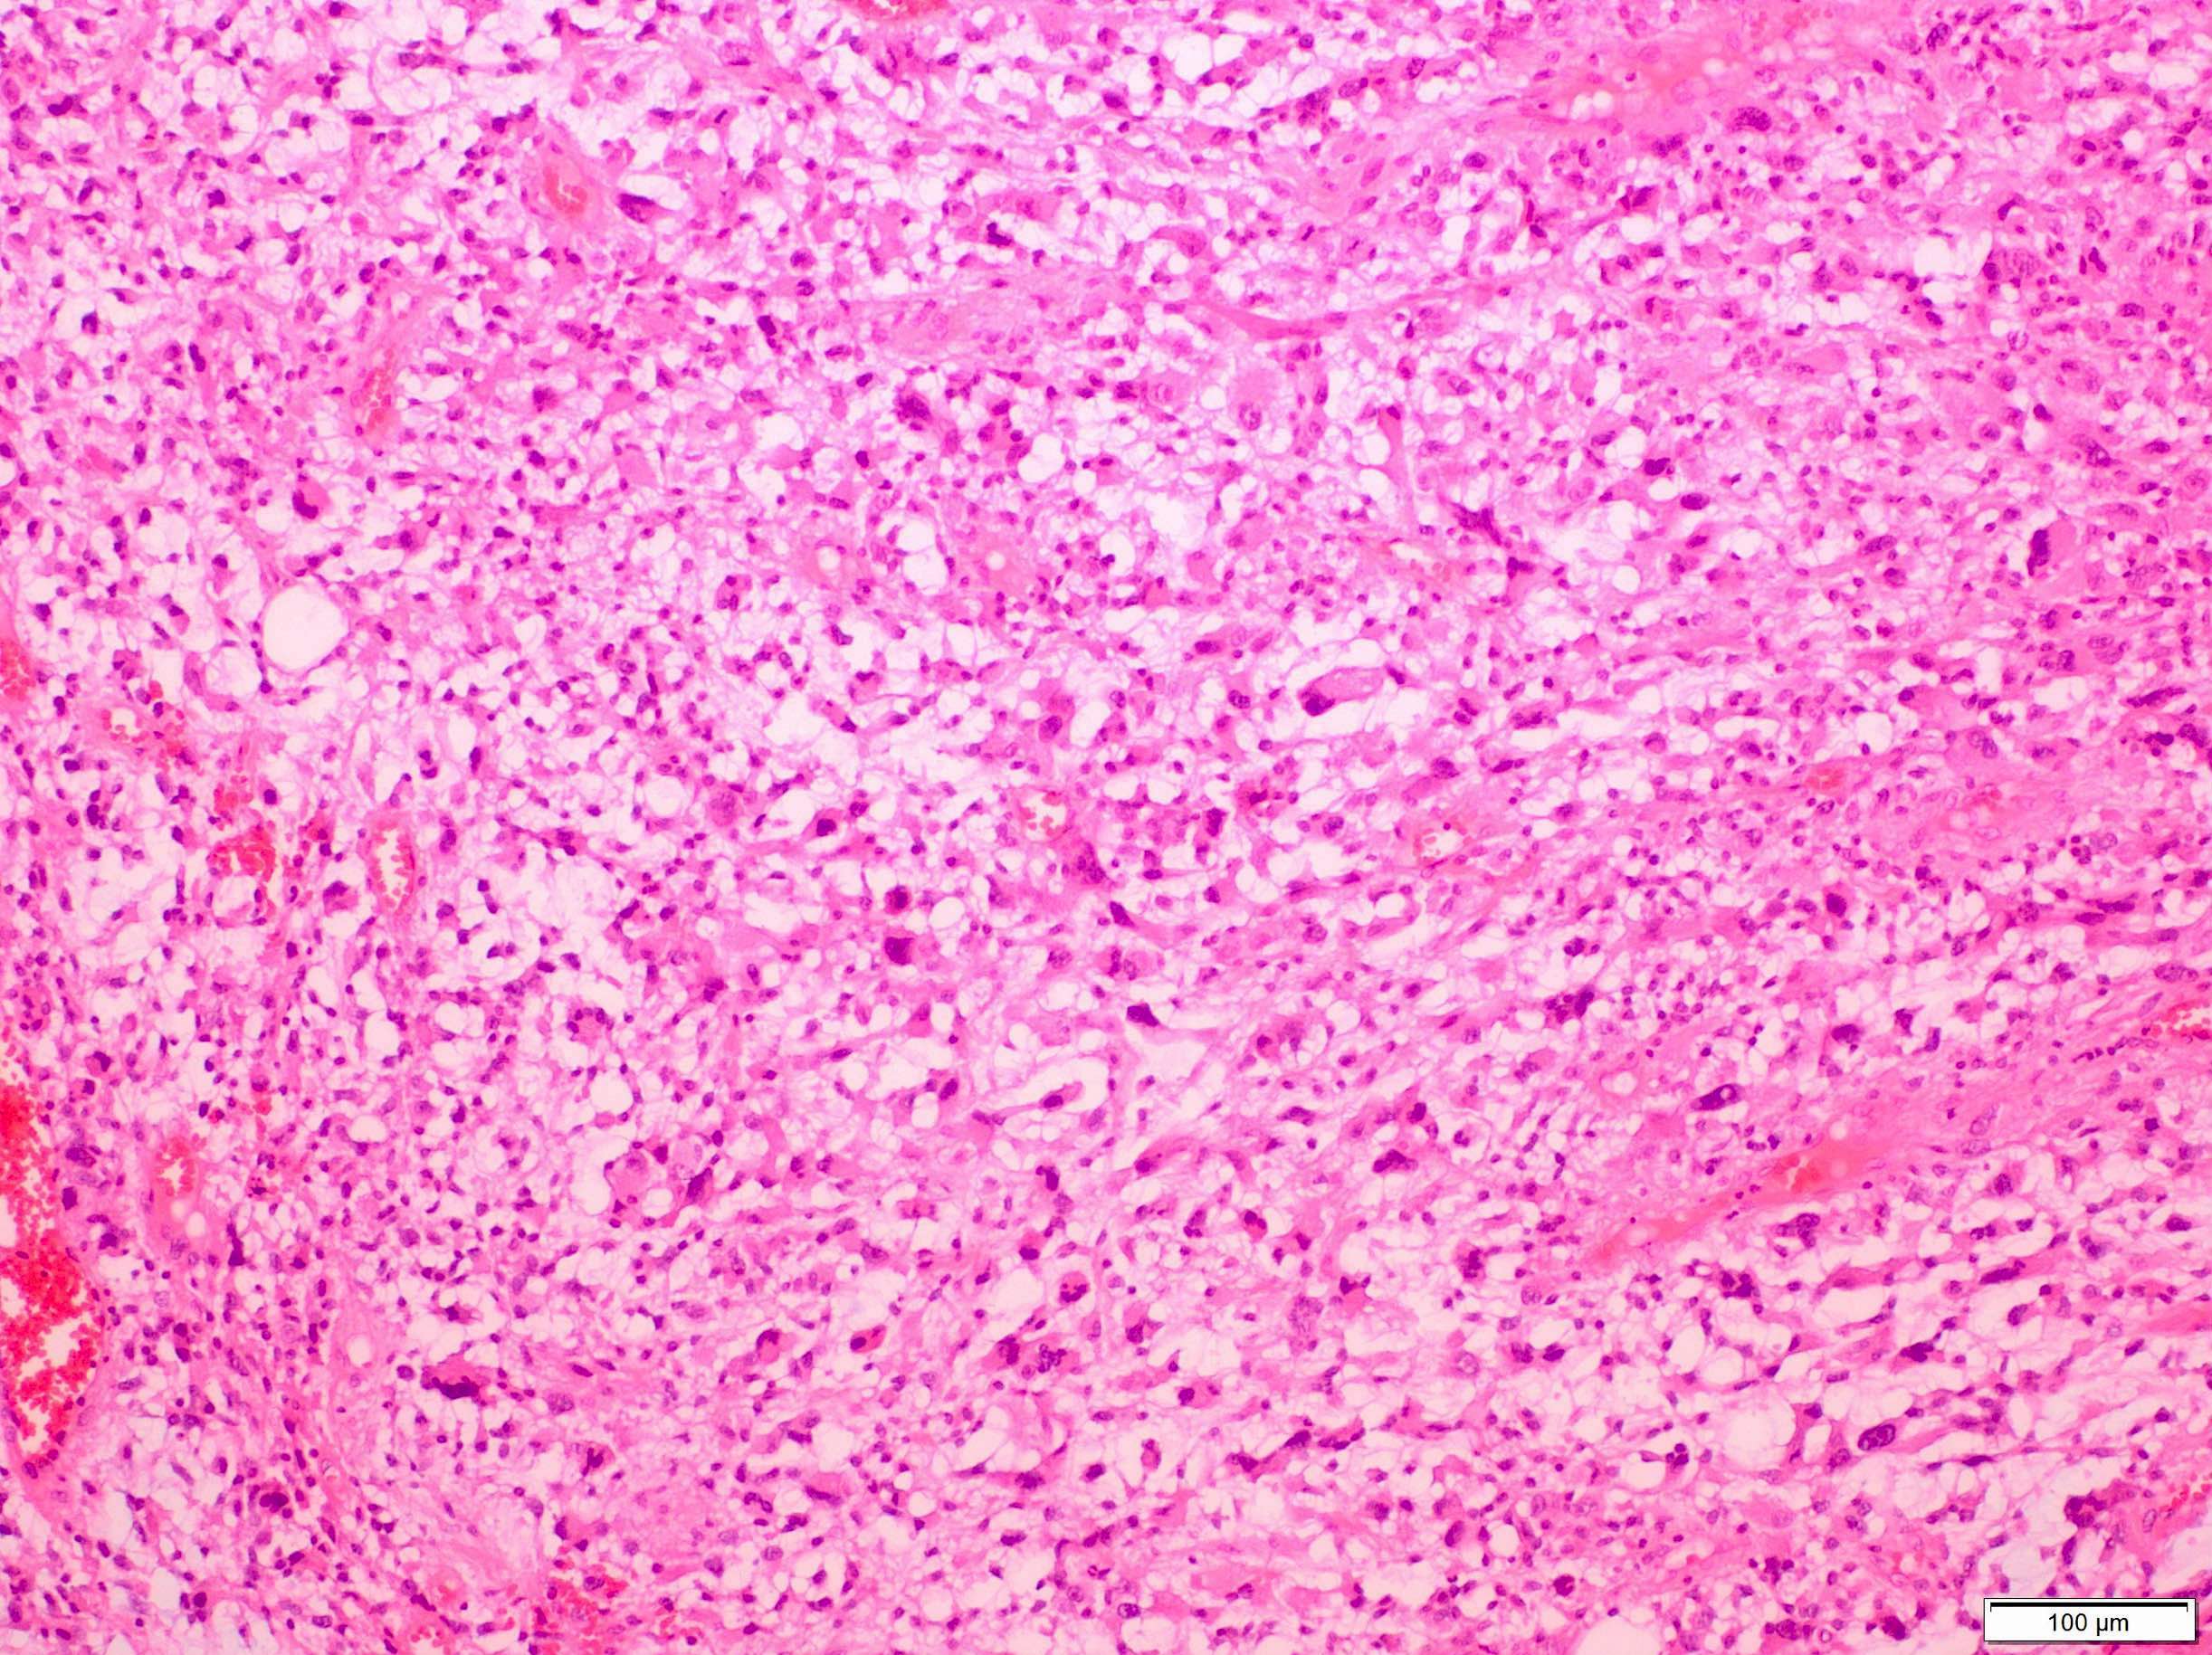

Microscopic (histologic) description

- Sheets of large, atypical and frequently multinucleated polygonal, spindled or rhabdoid eosinophilic cells (Am J Surg Pathol 2009;33:1850)

- Cross striations are seldom detected

Microscopic (histologic) images